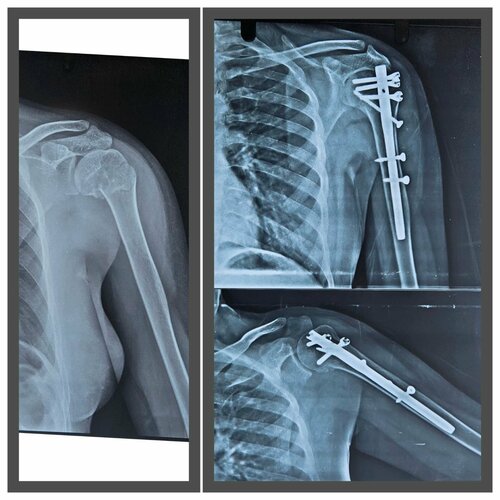

Minimally Invasive Humerus Fracture Treatment by Dr. Sonal Bansal

Dr. Sonal Bansal, Consultant Orthopedic Surgeon in Nerul, successfully treated a fracture of the head of the humerus using minimally invasive humerus ...